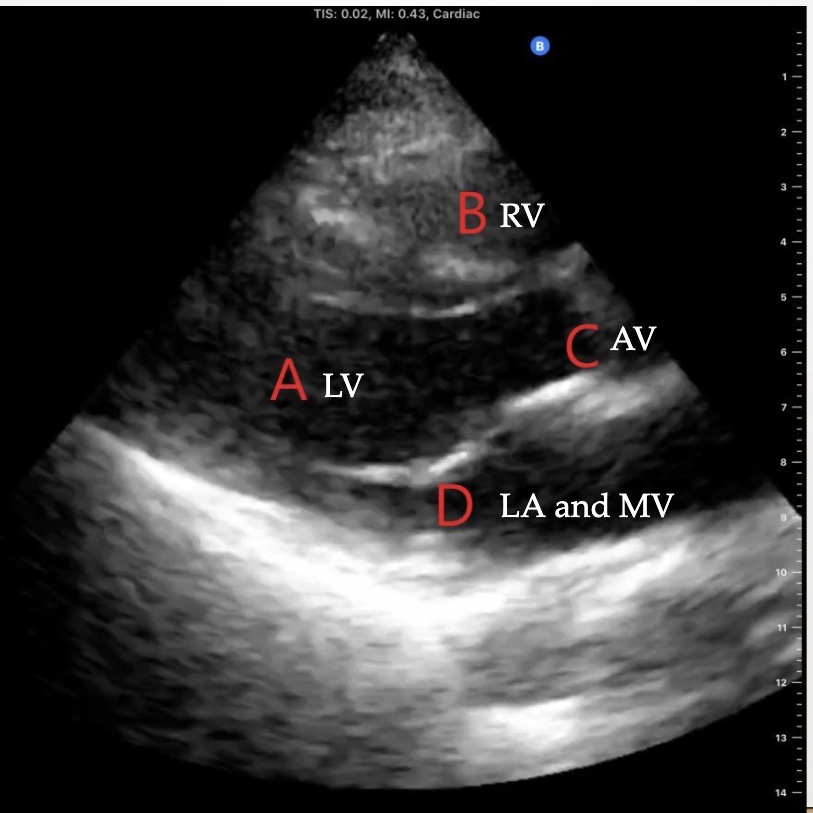

Identify the view and the structures on this echo

Parasternal long axis (PLAX)

What echocardiographic view will this obtain?

Parasternal short axis (PSAX)